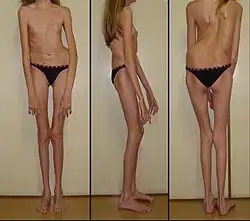

Marfan syndrome (MFS) is a multi-systemic genetic disorder that affects the connective tissue.[6][7][1] Those with the condition tend to be tall and thin, with long arms, legs, fingers, and toes.[1] They also typically have exceptionally flexible joints and abnormally curved spines.[1] The most serious complications involve the heart and aorta, with an increased risk of mitral valve prolapse and aortic aneurysm.[1][8] The lungs, eyes, bones, and the covering of the spinal cord are also commonly affected.[1] The severity of the symptoms is variable.[1]

Skeletal system

Most of the readily visible signs are associated with the skeletal system. Many people with Marfan syndrome grow to above-average height, and some have disproportionately long, slender limbs with thin, weak wrists and long fingers and toes.

Besides affecting height and limb proportions, people with Marfan syndrome may have abnormal lateral curvature of the spine scoliosis, thoracic lordosis, abnormal indentation (pectus excavatum) or protrusion (pectus carinatum) of the sternum, abnormal joint flexibility, a high-arched palate with crowded teeth and an overbite, flat feet, hammer toes, stooped shoulders, and unexplained stretch marks on the skin. It can also cause pain in the joints, bones, and muscles. Some people with Marfan have speech disorders resulting from symptomatic high palates and small jaws. Early osteoarthritis may occur. Other signs include limited range of motion in the hips due to the femoral head protruding into abnormally deep hip sockets.[16][17]